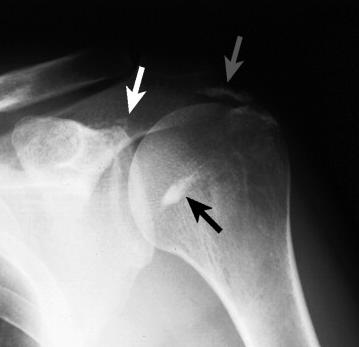

이러한 칼슘은 생기는 위치에 따라 증상이 다를 수 있는데 주로 회전근개의 부착부분에 생기기 때문에, (주로 Supraspinatus)

오구돌기 아래부분의 충돌이 있게 됩니다.

칼슘이 바로 똑 하고 생기는 것이 아니기 때문에 질병의 진행단계는

-칼슘전기(전석회화시기) : 통증X, metaplasia 시작

-칼슘기(석회화기) : 칼슘이 형성되고, 혈관이 생기는 단계

-칼슘후기(후석회화기) : 대식구가 작용하며, 매우 통증이 심한 단계

로 나뉠 수 있습니다.